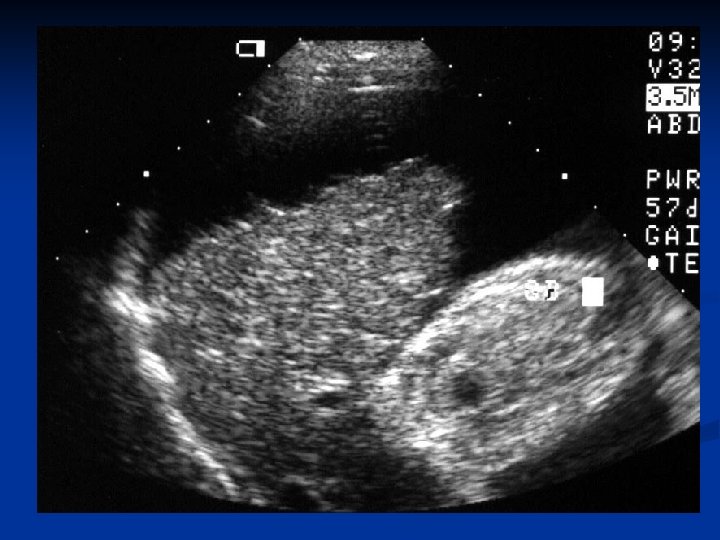

Через 6 месяцев у всех пациентов перенесших эмболизацию селезеночной артерии показатели крови в пределах нормы либо на субнормальном уровне. У всех больных при ФЭГС и рентгенконтрастном исследовании пищевода отмечается снижение степени варикозного расширения вен на один уровень. При контрольном УЗИ исследовании отмечено уменьшение размеров селезенки у 18 больных на четверть, а у 3 на треть от исходных. В 17 случаях отмечена стабилизация цирротического процесса с отсутствием асцита, присутствовавшего до эмболизации.

Вид пищевода до эмболизации селезеночной артерии

Вид пищевода после эмболизации селезеночной артерии